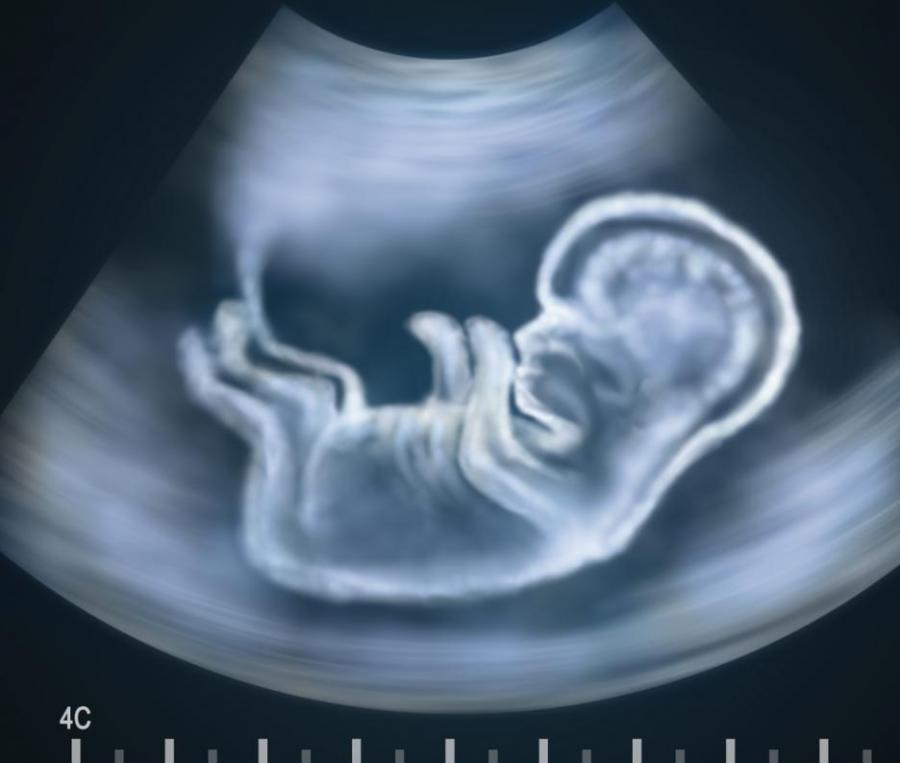

Шизофренията се причинява по време на бременността?

Точните причини за развитието на шизофренията продължават да остават до голяма степен мистерия, но една от посоките, в които са насочени усилията на учените, е връзката между бременността и отключването на болестта.

Учените отдавна разглеждаха възможността шизофренията да се окаже нервнодегенеративно заболяване, което се причинява по време на бременността или съвсем скоро след раждането, но и досега не бяха ясни истинските причини за проблема, както и точния механизъм на причиняването.

Някои от досегашните изследвания показаха, че болестта може да се дължи 80% на генетични причини. Други откриха, че усложнения в ранния период от живота могат да увеличат риска от развиването й до цели два пъти. Но новото изследване показа, че по време на някои усложнени бременности, като например когато майката хване вирусна инфекция, това може да доведе до поредица от събития, които да причинят болестта в някои случаи. Тогава някои свързани с шизофренията гени се отключват в плацентата на майката и засягат нейното състояние. В резултат това може да засегне ранното развитие на мозъка на плода.